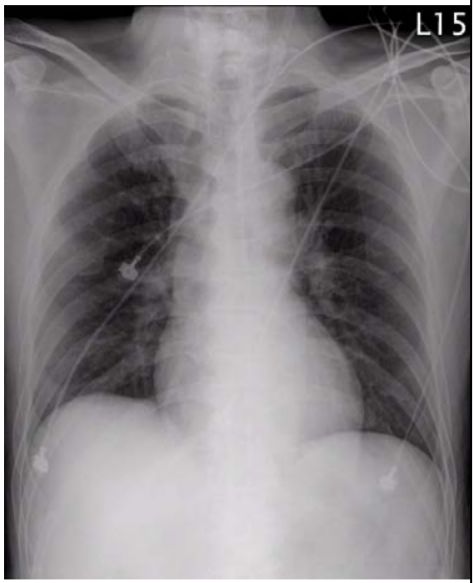

5. 病人男性59歲於午夜24時,突因胸悶並有牙床緊疼,乃直往急診部求診,時病人之T/P/R = 35.1/51/18, BP 137/74 mmHg; 理學檢查,未見任何異常。病史追尋,本病人曾經醫師確定高血壓、高脂血、糖尿病及攝護腺肥大,唯僅只服用Bisoprolol 2.5 mg/day。經緊急檢查:其心電圖及胸部X光顯示如圖:生化檢查: CK,96 U/L;CK-MB,20 U/L;TnI <0.0012 ng/ml;Sugar 252 mg/dL; Na,137 mmol/L; K, 3.7 mmol/L; TG,182 mg/dL and Total cholesterol, 222 mg/dL ; 血液檢查: Hb,13.9 g/dl; Platelet, 203 K/uL; WBC,9.45 K/uL; Cre,1.3 mg/dL 請問本病人最可能的急診診斷是:

(A) Printzmetal's angina (B) Aortic dissection (C) Acute anterior myocardial infarction (D) Hypertension (E) Acute periodontitis disease